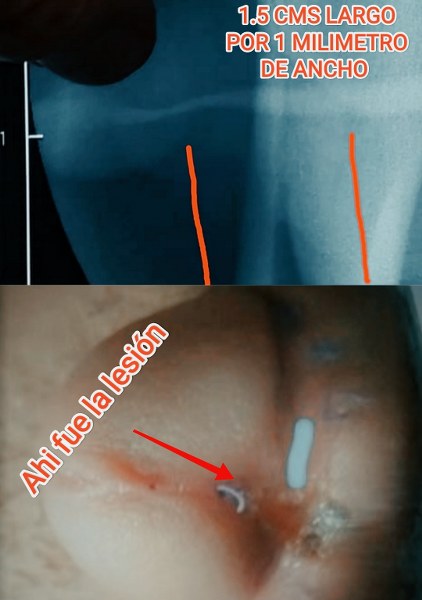

CAN YOU IMAGINE HOW MY KIDNEYS HAVE BEEN FORCING FOR 8 YEARS, I KNOW THAT I HAVE A DAMAGE BUT ROMAN CARVAJAL GARCIA WAS THE PRESIDENT OF THE THE "CONAMEU AND SMU" NATIONAL MEXICAN COMISSION OF UROLOGY AND MEXICAN SOCIETY OF UROLOGY , THE FIRST MUTILATION WAS IN HIS CLINIC "UCORE" IN ZAPOPAN JALISCO, HE HAS A LOT OF POWER THAT´S WHY I WANT TO TAKE THIS TO AN INTERNATIONAL COURT WHERE HE HAS NO POWER OR PLACE THIS IN A DOCUMENTARY, IT IS NOT COMMON TO PRACTICE GENITAL MUTILATION IN THE XX1 CENTURY IT IS NOT PRACTICE ANYMORE EVEN IN WAR, I NEED AN URETHRAL RECONSTRUCTION, THE MEXICAN UROLOGIST THAT HAVE SEEN THIS THEY HAVE TOLD ME THAT HAVING A 1.5 CENTIMETERS LONG WITH 1.2 MILIMETERS WIDE ESTENOSIS IS "NORMAL" I HAVE RECORDED EVERY CONSULTATION WITH A MINI AUDIO DIGITAL RECORDING DEVICE IN MEXICO IT IS LEGAL RECORDING A CONSULTATION I HAVE A LOT OF EVIDENCE

IN THIS PICTURE YOU CAN SEE HOW IT LOOKS THE PENIS BASE IN A NORMAL PENIS AND APPRECIATE HOW IT LOOKS MY PENIS BASE, THE PENIS BASE IS WHERE YOU ACCOMPLISH A RIGID ERECTION IT IS NOT AN EASY SURGERY YOU CAN SEE A NORMAL PENIS IN THE PICTURE BELOW AND THE SECOND PIC IS WHAT I HAD LEFT AS PENIS I NEED A GENITAL RECONSTRUCTION

YOU CAN SEE IN THE ABOVE PIC WHERE YOU REMOVE SKIN IN A CIRCUNCISION WHY THESE CRIMINAL DOCTORS REMOVED SKIN FROM MY PENO-ESCROTAL JUNCTION? IT WAS NOT AN ACCIDENT IT WAS A CRIME AGAINST ME